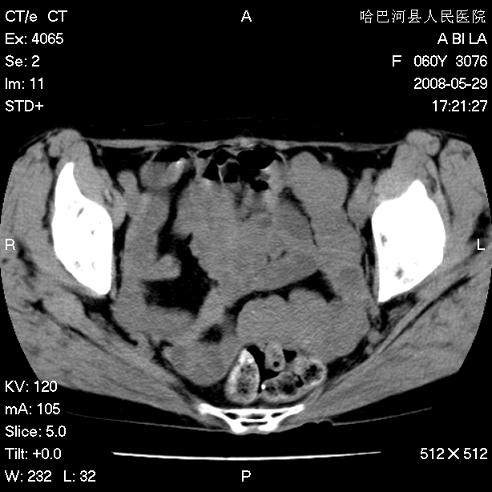

标题: CT13730:排尿不畅4天,抗炎治疗无效,现尿中可见血块 [打印本页]

标题: CT13730:排尿不畅4天,抗炎治疗无效,现尿中可见血块

手术结果及病理:膀胱癌并膀胱壁转移,膀胱内血块